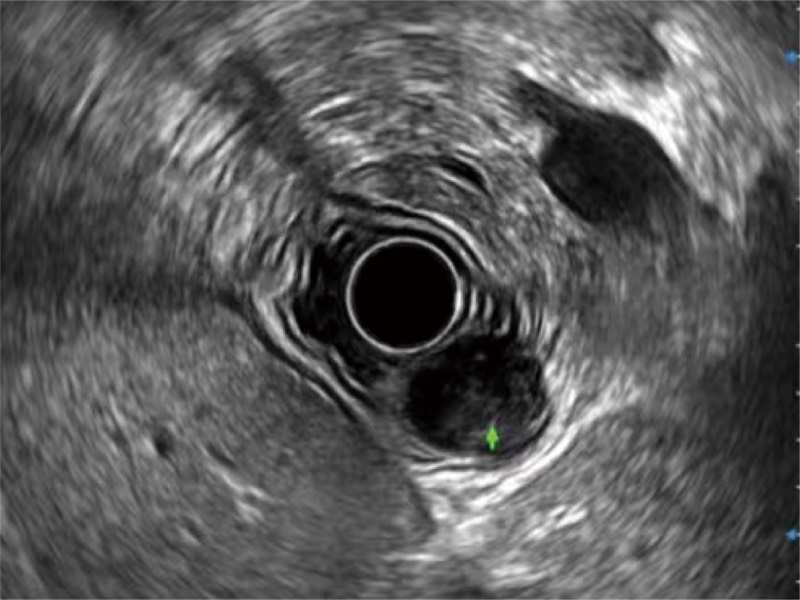

食管内间质瘤清晰显像

清晰显示胆总管及周围血管分布